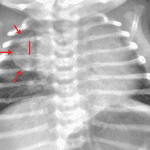

- Right posterior mediastinal mass measuring approximately 2.5 x 2.5 cm on the frontal view with associated rib splaying (right third and fourth ribs) and anterior displacement of the trachea

- No focal airspace opacification, pleural effusion, or pneumothorax

- Normal size and configuration of the cardiothymic silhouette

- Posterior mediastinal mass (thoracic neuroblastoma)

Right posterior mediastinal mass measuring approximately 2.5 x 2.5 cm on the frontal view with associated splaying of the right third and fourth ribs and anterior displacement of the trachea. Recommend chest CT for further evaluation.

No focal airspace opacification, pleural effusion, or pneumothorax.

Normal size and configuration of the cardiothymic silhouette.